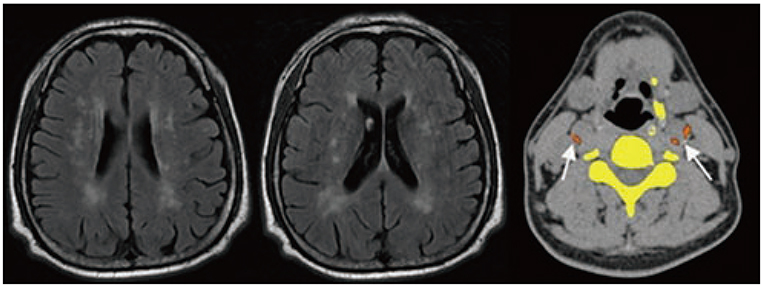

This study involved retrospective evaluation of 60 OSA patients who underwent both upper airway CT and brain MRI. Using polysomnography, several indicators, including apnea index (AI), were used to evaluate the relationship between OSA and silent cerebrovascular lesions. The CarACS was quantified on CT imaging using the modified Agatston method. Silent cerebrovascular lesions were evaluated on brain MRI by grading periventricular hyperintensity (PVH). Various clinical characteristics, including age, were analyzed in each patient.

RESULTS

The number of patients per PVH grade 0, 1, 2, 3, and 4 was 26 (43.3%), 14 (23.3%), 14 (23.3%), 4 (6.7%), and 2 (3.3%), respectively. The mean age, hypertension, smoking status, AI, and CarACS were significantly different among PVH groups (Ps < 0.05). In univariate analysis, the presence of carotid arterial calcification (β = 0.483, p < 0.01), CarACS (β = 0.482, p < 0.01), and age (β = 0.360, p < 0.01) showed a significant association with PVH grade. The mean AI and lowest O₂ saturation had statistically weak associations with PVH grade (β = 0.267, p < 0.01; β = −0.219, p < 0.14, respectively). In multivariate analysis, CarACS was the only factor affecting PVH grade (p < 0.04).

CarACS is associated with the severity of silent cerebrovascular lesions. Therefore, additional analysis of CarACS in OSA patients may provide more information on their cerebrovascular status.